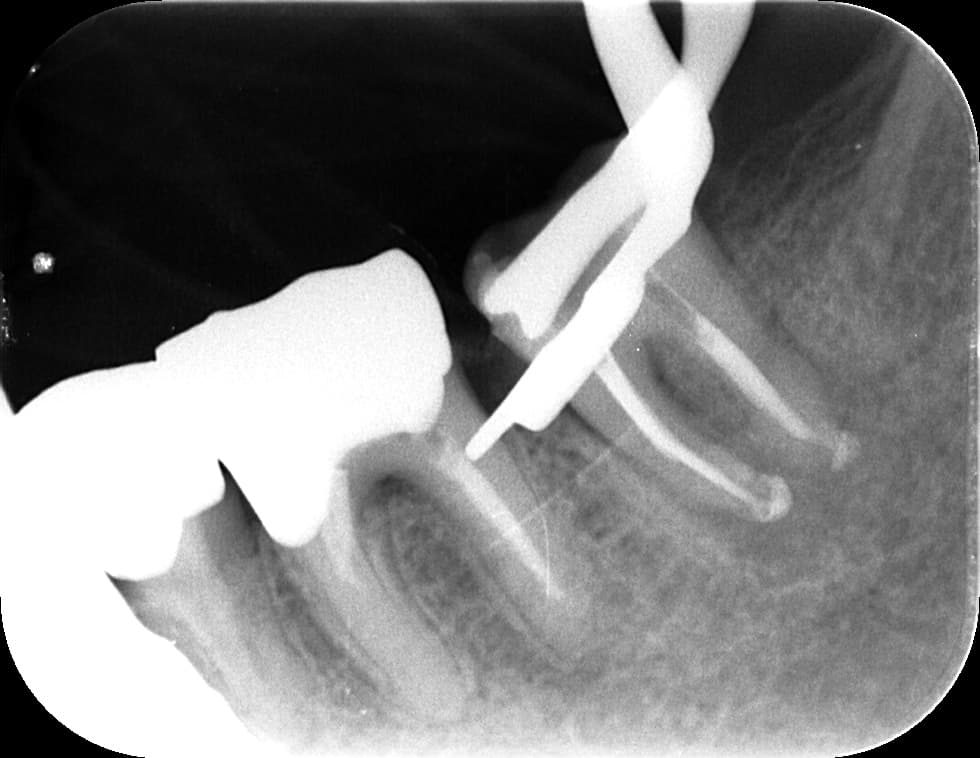

3. 矯正治療前に根管治療を済ませたほうがよい理由

矯正中は歯が動くため、弱っている歯や神経が炎症を起こしやすい時期です。特に、以下のような歯は矯正前に治療した方が安心です。

・大きな虫歯がある

・神経まで深い虫歯が近い

・すでに痛みを繰り返している

・歯髄の炎症が疑われる

・過去の治療が不十分

このような歯をそのまま矯正に進むと、矯正中に 「急に痛みが出る」「歯がしみる」「咬めない」 といったトラブルが発生しやすくなります。

矯正中は器具がついているため治療が難しくなり、治療計画全体が遅れるケースもあります。

そのため、矯正前に “怪しい歯は先に治療しておく” ことが、矯正期間をスムーズに進めるための重要な準備です。

② 治療すべき歯は矯正前に治療

・根管治療

・大きな虫歯

・適合不良の詰め物

矯正中に痛みを出さないことが、治療の成功に直結します。